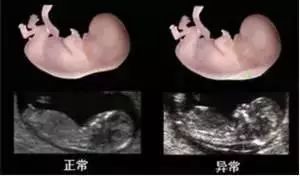

(图:NT检查的正常与异常的比较)

NT检查结果异常怎么办?

孕妇进行NT检查后拿到的结果通常只显示NT值多少,现在的正式报告是会显示风险值,会更准确、更客观。最早期的NT检查结果是根据NT正常值来判断,不超过为3mm为正常,准确来说应该是要将资料输入系统,由FMF授权使用的孕早期筛查风险计算软件进行计算,从而综合评估风险。